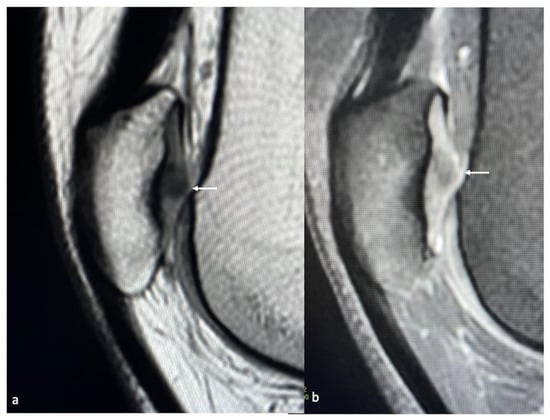

- Kijowski, R.; de Smet, A.A. MRI Findings of Osteochondritis Dissecans of the Capitellum with Surgical Correlation. Am. J. Roentgenol. 2005, 185, 1453–1459. [Google Scholar] [CrossRef]

- Takahara, M.; Ogino, T.; Takagi, M.; Tsuchida, H.; Orui, H.; Nambu, T. Natural Progression of Osteochondritis Dissecans of the Humeral Capitellum: Initial Observations. Radiology 2000, 216, 207–212. [Google Scholar] [CrossRef]

- Schenck, R.C.; Goodnight, J.M. Osteochondritis dissecans. J. Bone Jt. Surg. Am. 1996, 78, 439–456. [Google Scholar] [CrossRef]